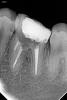

Kolchanov Опубликовано 22 февраля, 2013 Автор Поделиться Опубликовано 22 февраля, 2013 Себе бы в каналы лазить не дал Нахлобучил бы литой коронкой, арцы и в воду концы. Короче залез я туда. Полость зуба была забита каким-то удивительным йодоформным цементом. Дистальный нашелся легко, что не удивительно при таких размерах. Пульпы там живой не было, так мумие какое-то. С мезиальными пока загвоздка - заросли, паскуды. Наверное все-таки не в пролом году этот зуб тиранили. Ссылка на комментарий

Kolchanov Опубликовано 10 апреля, 2013 Автор Поделиться Опубликовано 10 апреля, 2013 Вот такая вот фигня с этим зубом получилась. Надо оно было ему, нет, теперь уже все равно.С гидороокисью в дистальном она походила с месяцок+ сегодня удалось таки залезть в мезиально-язычный. Мезиально-щечный долбил пока видел, а потом плюнул. Там и так фуркация слезами плачет, судя по снимку.Передал отправил к ортопедам. Чую штамп будет там... Ссылка на комментарий